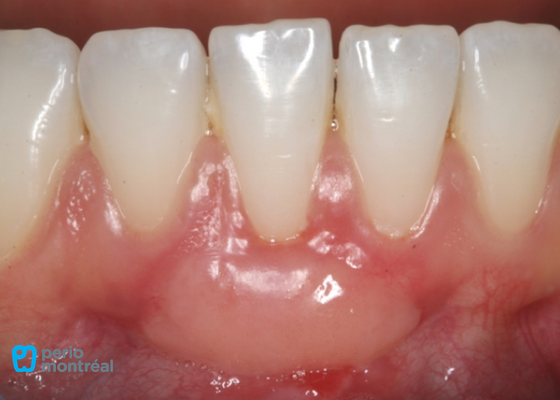

1 Week Post-Op

1 Month Post-Op